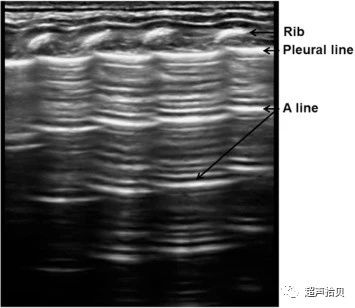

图1

正常肺部超声检查发现新生儿(胎龄37周+4;出生体重2,970克)因出现病理性黄疸而在出生后3天住院。 胸膜线和A线平滑,清晰,相互平行,没有B线或彗尾